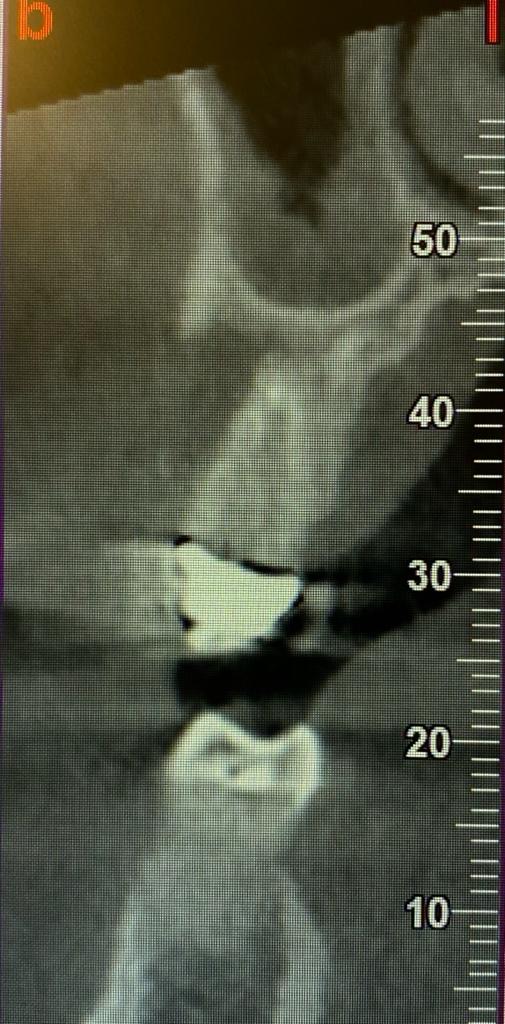

Dalla radiografia 3D, in questo caso, è emersa una situazione completamente differente. Il paziente presentava una reazione infiammatoria con riassorbimento dell’osso periradicolare, probabilmente di origine traumatica o endodontica.

Grazie alla ConeBeam sul paziente è stata effettuata prima una estrazione e poi la conseguente rigenerazione ossea con biomateriali e membrana, che consentirà, poi, l’inserimento di un impianto.